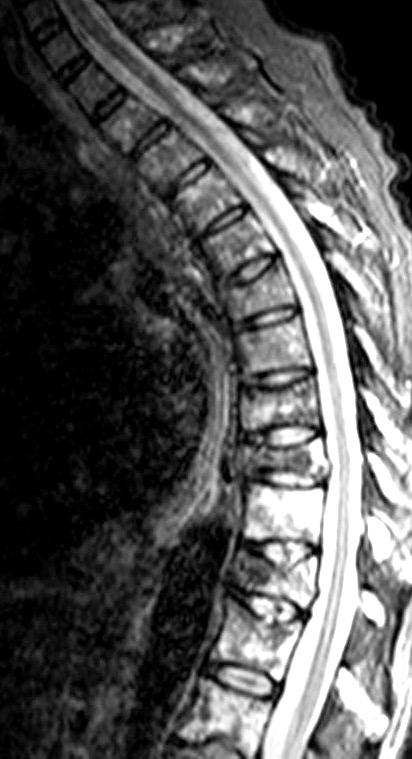

Surek J et al. MRI in patients with tuberculous spondylitis presenting as vertebra plana: a retrospective analysis and review of literature . Clin Radiol 2013

Fracturas dorsales

Wu M.-H., Huang T.-J., Cheng C.-C., Li Y.-Y., Hsu R.W.-W. Role of the supine lateral radiograph of the spine in vertebroplasty for osteoporotic vertebral compression fracture: A prospective study. BMC Musculoskelet. Disord. 2010;